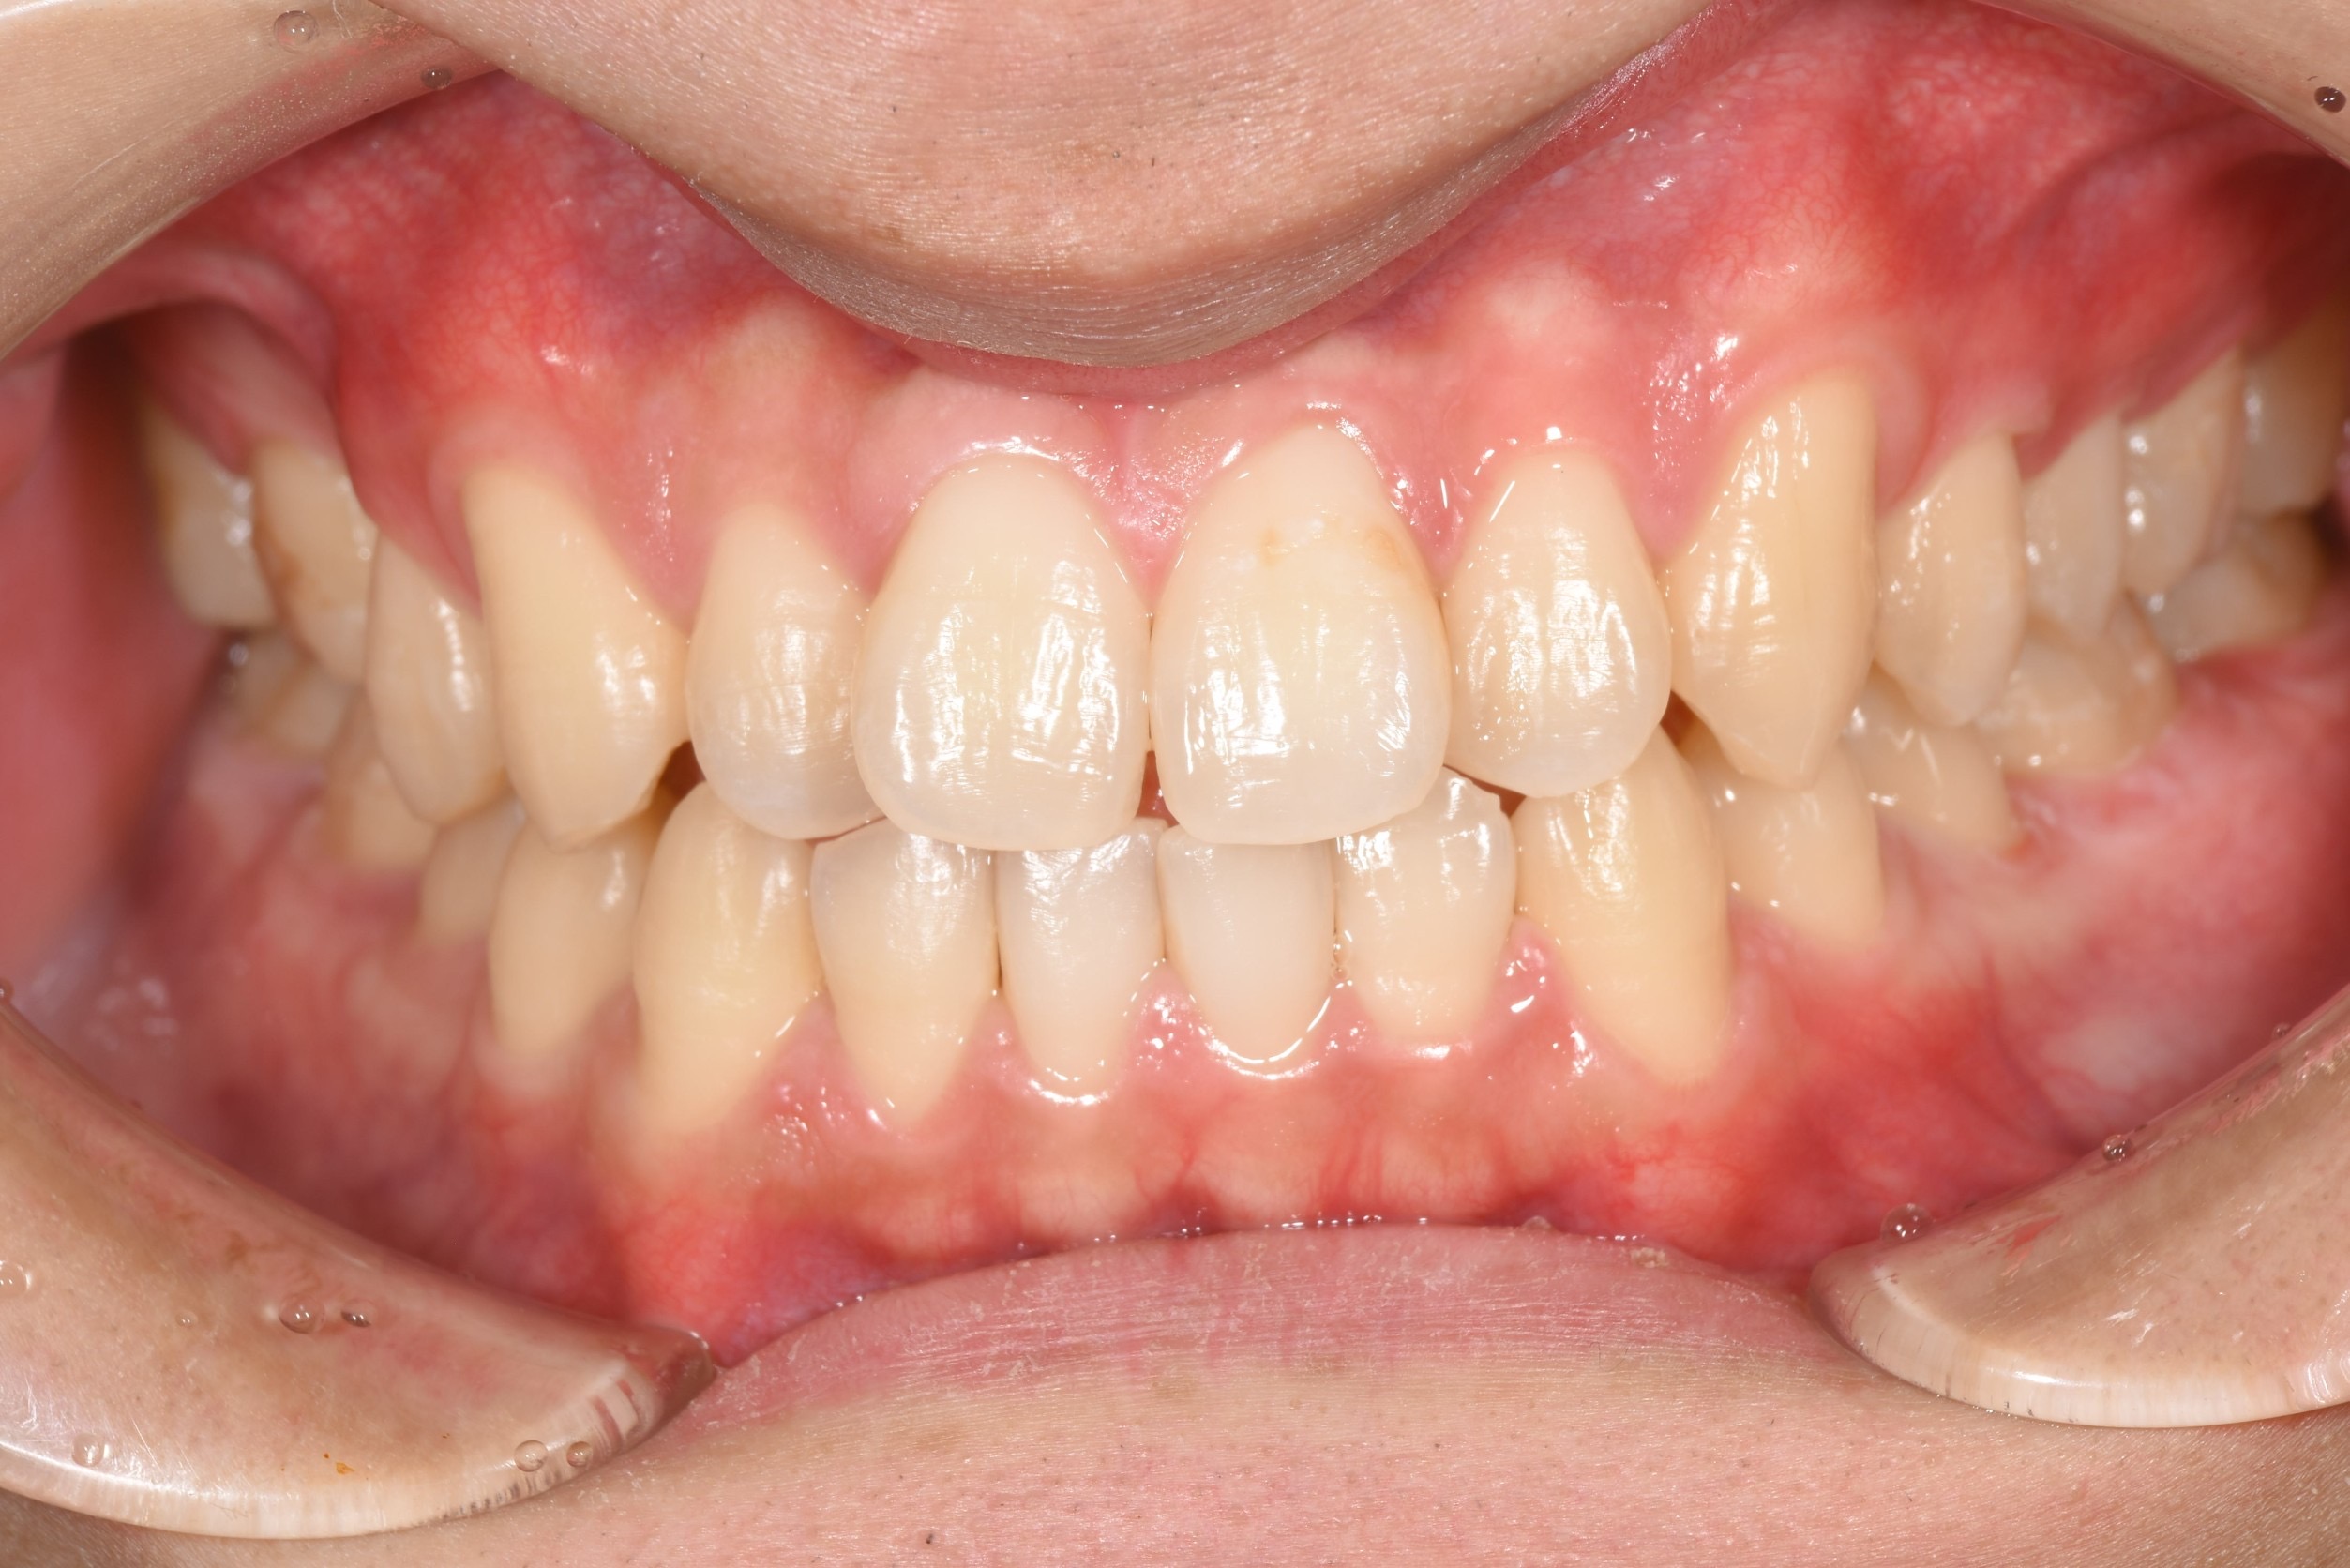

• 前歯のインプラント抜歯即時埋入

前歯のインプラント抜歯即時埋入

• インプラント抜歯即時埋入

インプラント抜歯即時埋入